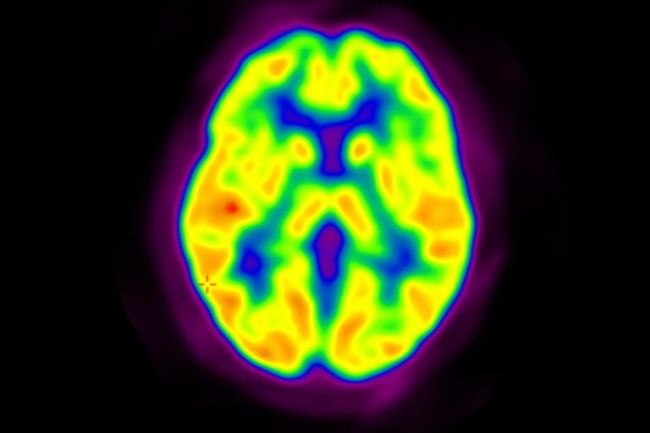

محققان موفق به کشف ربط تازه بین ساختار مغز و اوتیسم شدند_رنگو

[ad_1] نوشته و ویرایش شده توسط مجله ی رنگو برای دههها، محققان از مدلهای حیوانی و بازدید بافت مغز بعد از مرگ برای فهمیدن تفاوتهای مغزی در افراد مبتلا به اوتیسم منفعت گیری میکردند. اما اکنون، یک مطالعه پیشگامانه موفق شده است تا برای اولین بار، تفاوتهای مولکولی در مغز افراد زنده مبتلا به اوتیسم را شناسایی کند که مستقیماً با علائم مهم این اختلال مرتبط است. به نقل از دپارتمان اخبار علمی رسانه فناوری تکنا، سیناپسها، اتصالات کوچکی بین سلولهای عصبی می باشند که به گفتن پلهای ارتباطی عمل…